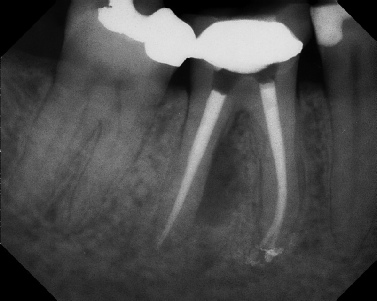

COMPLICATED ANATOMY LARGE LESIONS CALCIFIED CANALS PERFORATION / RESORPTION SEPARATED INSTRUMENTS SURGICAL CASES RETREATMENT / pOST REMOVAL OPEN APICES ACCESS THRU CROWNS Root Canal Case Portfolio

Pre-op Post-op 6 mos.